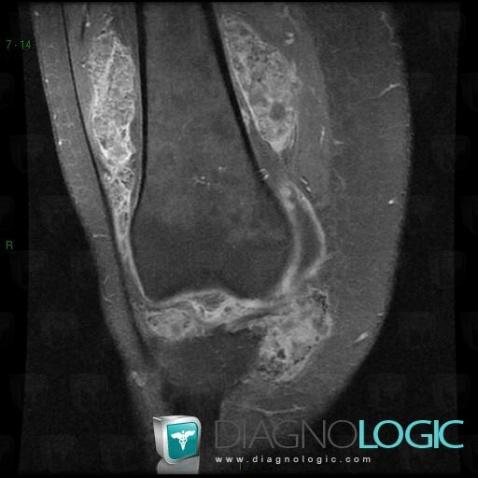

Ostéochondromatose synoviale, Articulations fémoro tibiales / Echancrure, Articulation fémoro patellaire, IRM

- Diagnostic Ostéochondromatose synoviale, Localisation(s) Articulations fémoro tibiales / Echancrure, comportant les gammes Lésions de la graisse de hoffaArticulation fémoro patellaire, comportant les gammes Masse des parties molles juxta articulaires, Arthropathie avec nodules des parties molles, Masse ou épaississement synovial